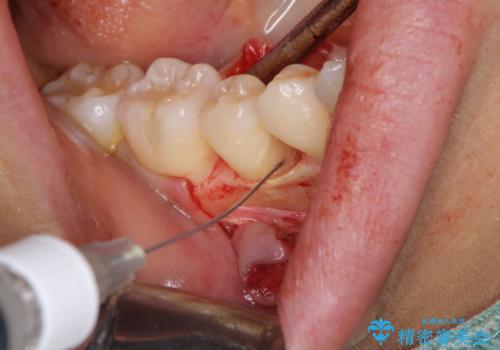

患者様は、他院で右下の歯を抜歯かもと言われました。全体の歯周病はなく、右下の1歯だけ骨が極端に減少していました(初診時歯周ポケット7mm。通常は3mm以下。)。その歯だけ咬合が強いことが原因と考えられたため、咬合を弱くする処置と減少した骨を再生する処置が必要になりました。

骨の再生治療手術をして10か月経過観察をしたのち、骨を平坦化する手術を行い、治療終了となりました。